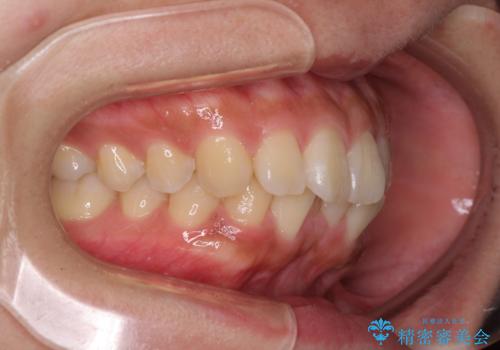

- 前歯の突出感を気にして来院された患者様です。

咬合力が非常に強く、咬合力で前歯が前方に押し広げられており、上下唇に閉じにくさが認められました。

上下左右の第一小臼歯4本を抜歯し、ワイヤー装置にて矯正治療を行うこととしました。

強い咬合力により前歯の隙間がなかなか閉じられず、治療期間は長いものとなりましたが、横顔の印象が大きく変わるほど口元の印象を改善することができました。